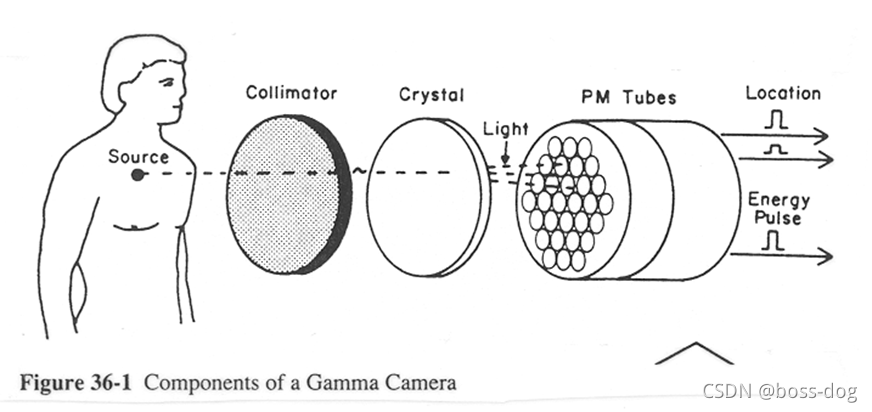

Gamma Camera/Scintillation Camera(核素成像)

4.核素成像(Radionuclide imaging)。有核辐射,需要采用高能量的X光或者伽马光子;应用领域如单光子平面或成像(Planar single photon imaging)、单光子发射的CT(Single Photon EmissionCT,SPECT)、正电子发射成像(Positron Emission Tonography),这三类都是需要通过往人体里面进行静脉注射一种核素,这种核素需要释放出光子或者释放出正电子来回到它的稳态,如果释放出光子,这光子高能光子穿过人体就会被探测器接收到,然后用来做成像。